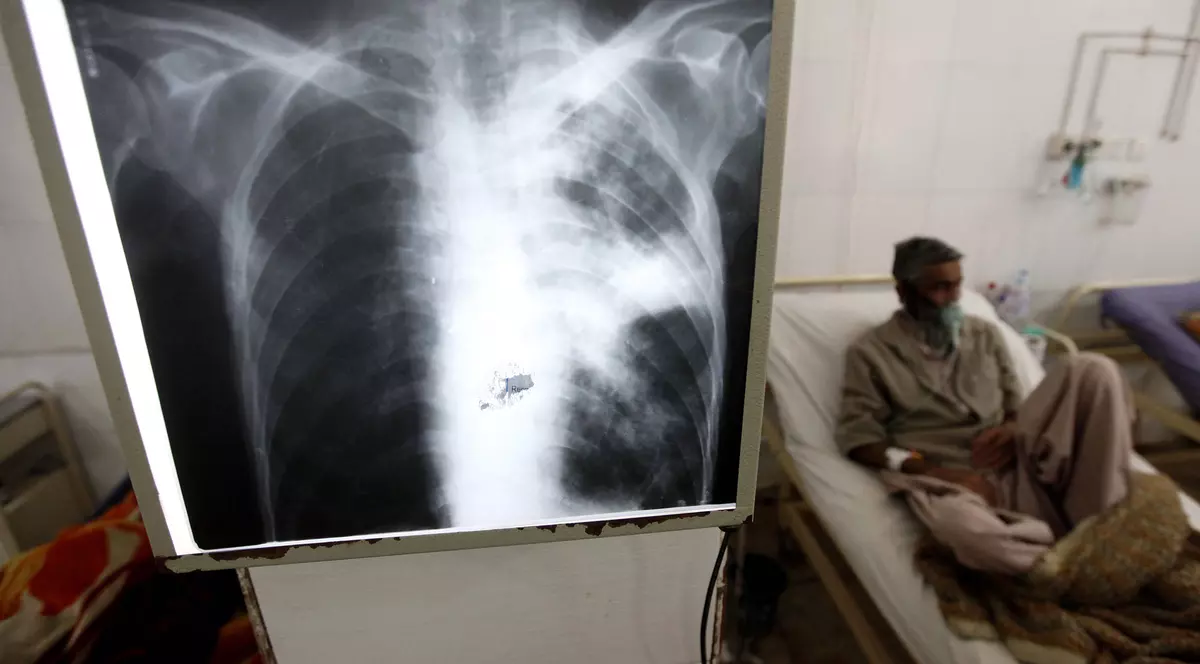

Măsurile și restricțiile luate în pandemia de COVID în România au adus și o scădere dramatică: de la 9.368 de cazuri de TBC diagnosticate în 2019 la puțin peste 6.000 identificate anul trecut. „Doar că cifrele nu arată adevărul”, spune Paula Rusu, activistă pentru drepturile persoanelor cu tuberculoză.

Datele INSP arată că astăzi, în România, sunt 7.221 de bolnavi de tuberculoză față de 11.000 acum doi ani. Realitatea e însă mult mai dureroasă.

Lipsa unui diagnostic TBC poate duce la decese. Un lucru care deja se întâmplă, explică Beatrice Mahler, managerul Institutului de Pneumoftiziologie Marius Nasta.

Doar în primele două luni din 2021, spitalul a avut internați patru copii cu forme grave de TBC. Unul dintre ei a murit.

„Sunt mai mulți copii cu TBC (263, conform INSP), dar aceste forme grave n-au fost de mult atât de multe. Când ai TBC formă severă la copii înseamnă că foarte mulți adulți sunt bolnavi în jurul lui și au venit târziu la doctor. Dacă depistezi adultul, poți depista rapid și copilul – ca să nu ajungă cu o formă severă”, explică Mahler.

În 2020, doar doi copii au fost internați la „Nasta” cu formă severă de TBC.